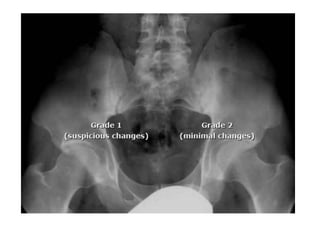

• The SI joint abnormalities are typically graded

to identify the nature and severity of

• Grade 0 : Normal.

• Grade 1: Suspicious(but not definite) changes

• Grade 2: minimal abnormality- small areas of

erosions or sclerosis without alteration of joint

width.

• The SIjoint abnormalities are typically graded to identify the nature and severity of involvement. • Grade 0 : Normal. • Grade 1: Suspicious(but not definite) changes • Grade 2: minimal abnormality- small areas of erosions or sclerosis without alteration of joint width.

• Grade 3:unequivocal abnormality – moderate or advanced sacroilitis with one or more of the following: erosions, sclerosis, joint space widening, narrowing, or partial ankylosis. • Grade 4: total ankylosis of joints